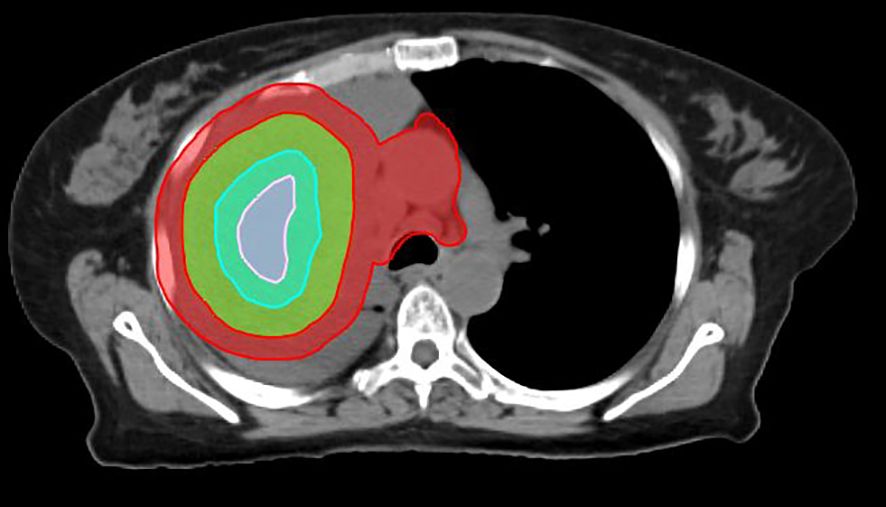

Early Experience with SBRT-based Partial Tumor irradiation targeting Hypoxic segment (SBRT-PATHY) of large bulky tumors.

Large bulky tumors possess poor prognostic characteristics that make tumor control difficult. SBRT-based Partial Tumor irradiation targeting Hypoxic segment (SBRT-PATHY) has been described as a spatially fractionated radiotherapy technique that induces both bystander and abscopal effects by sparing the peri-tumoral immune micro-environment thus minimizing the negative effects of radiation induced lymphopenia. The aim of these case reports is to present our early experience of 4 cases in the utilization of SBRT-PATHY at our institution.